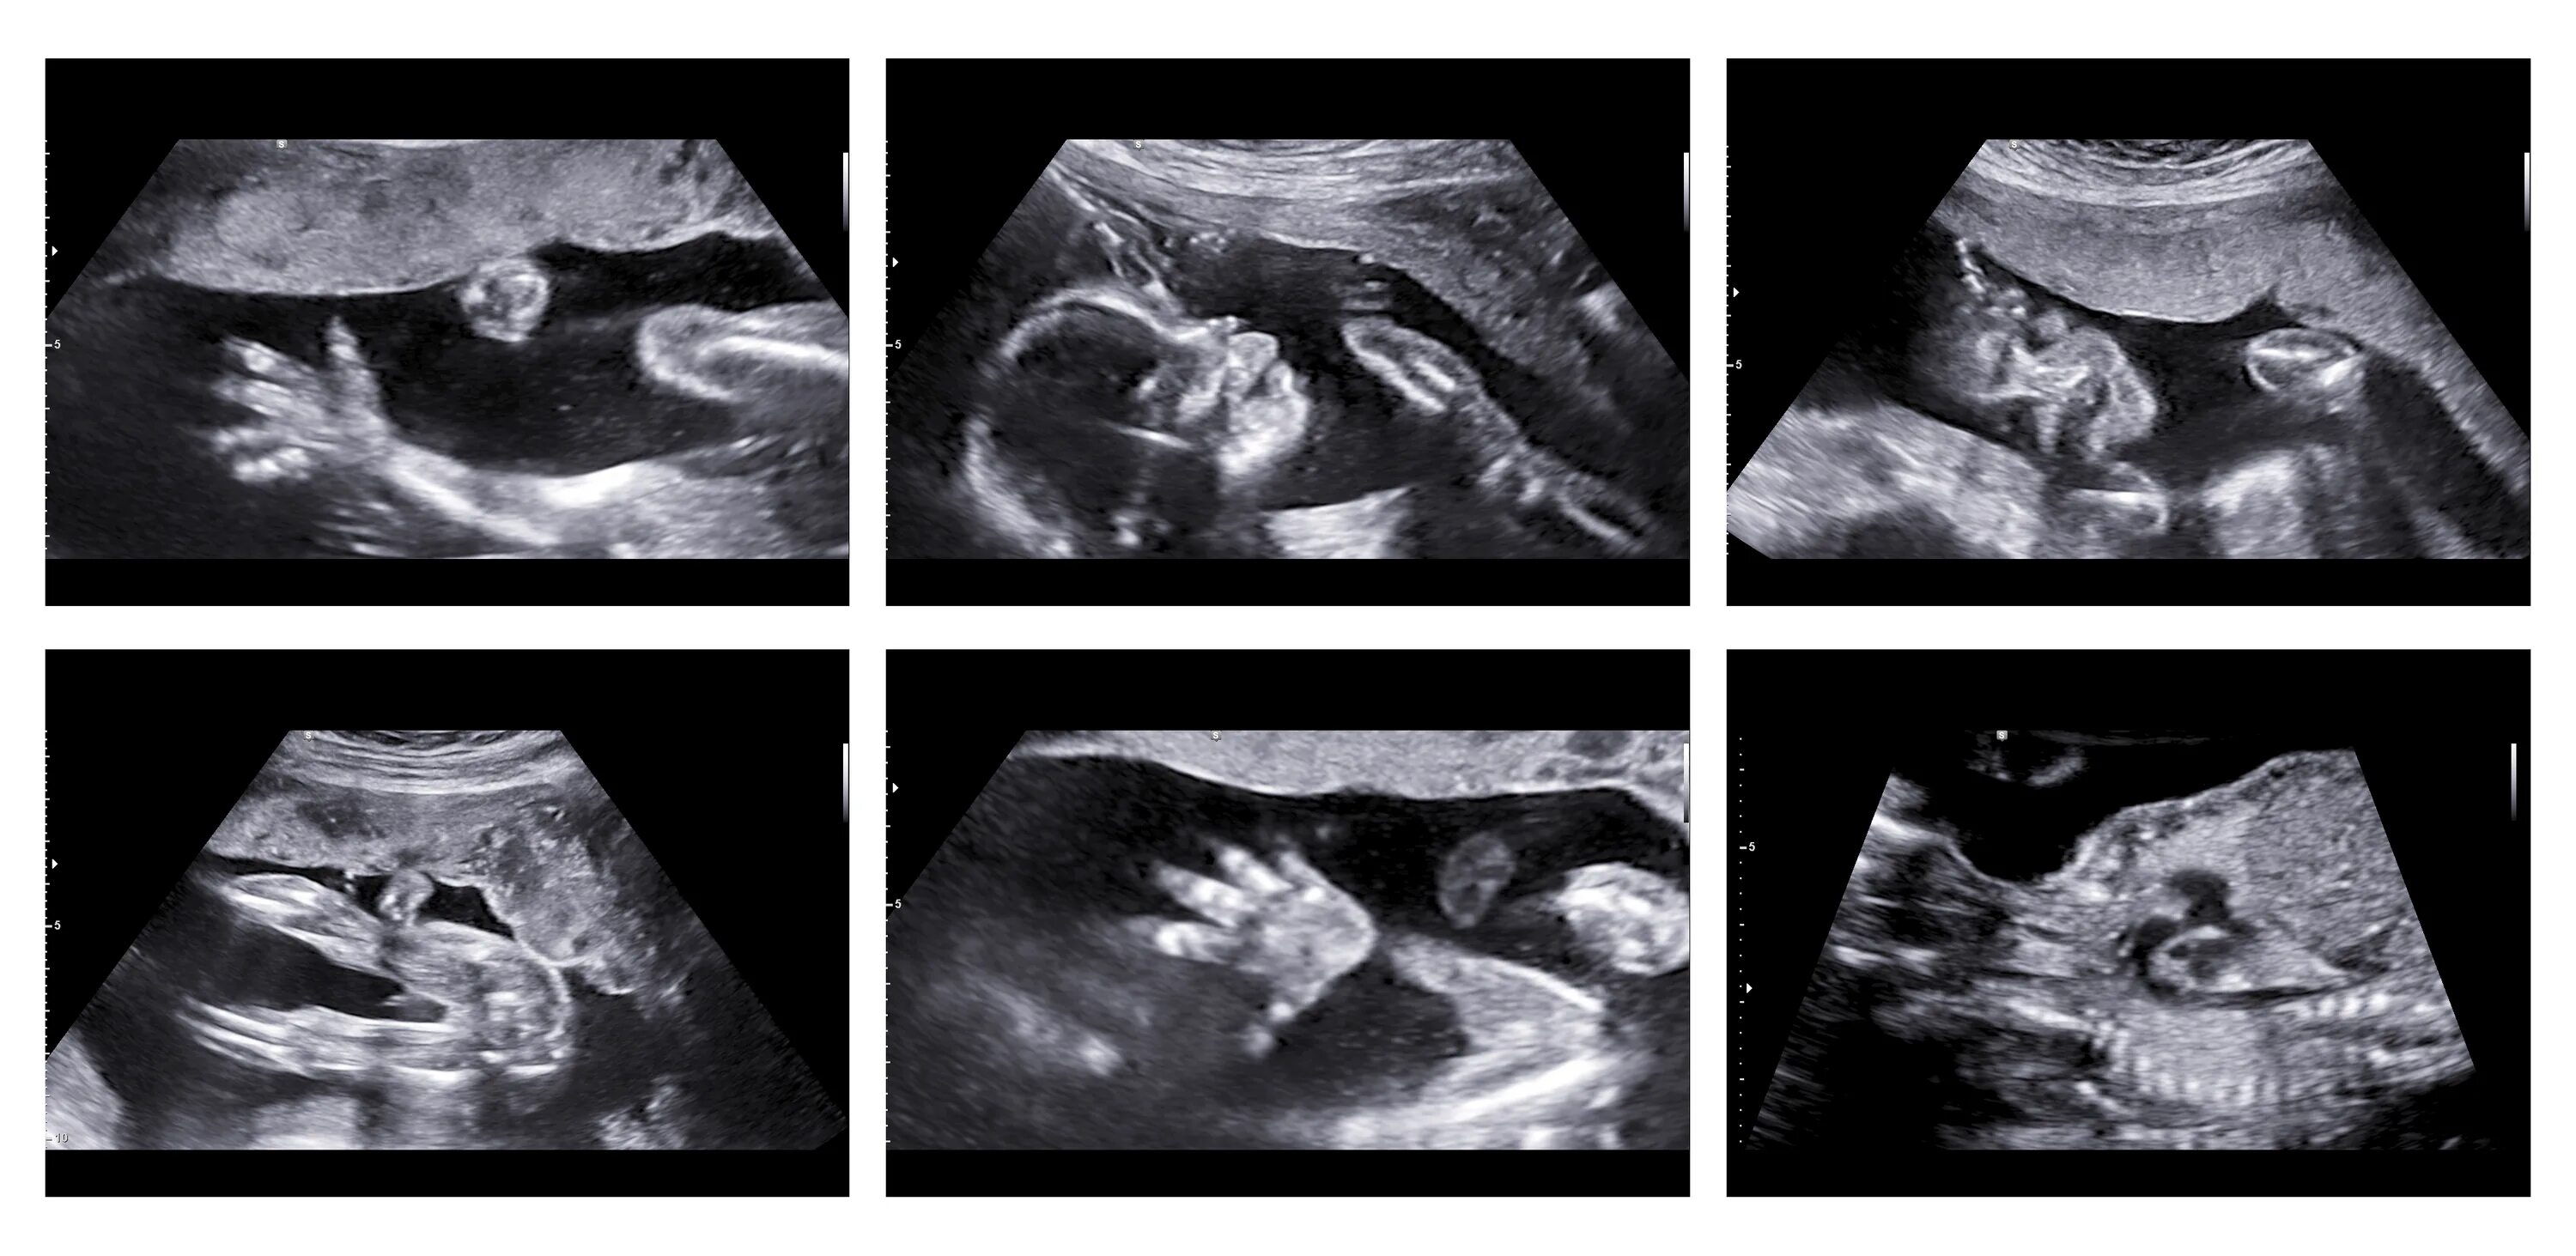

Два в триместре